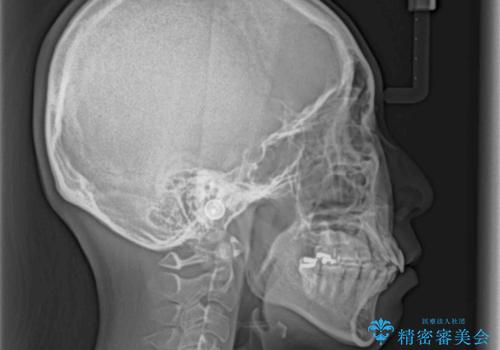

- 抜歯矯正の後戻りで前歯が突出してきていることを気にして来院された患者様です。

口元の突出感を改善するにあたり、抜歯矯正は行うことができないため、奥歯の後方移動とIPR(歯と歯の間を削る)により達成することとしました。

再度後戻りしたときに対応しやすいよう、インビザラインにて矯正治療を行うこととしました。